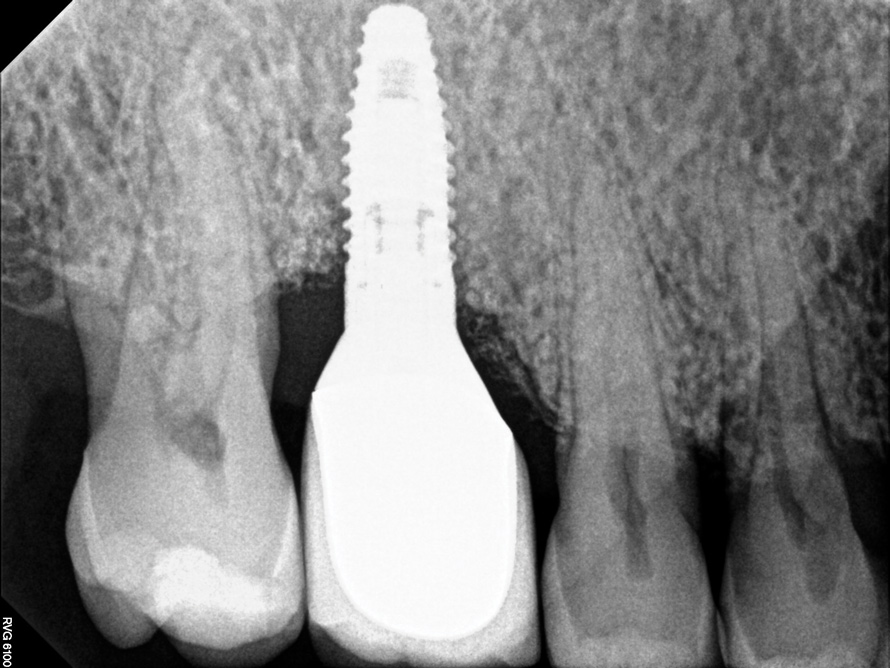

Following the diagnosis of peri-implantitis (Figure 5 and Figure 6), an initial evaluation of the affected implant fixture should be made to establish the rationale for treatment and whether removal of the implant is indicated. Although nonsurgical treatment of peri-implantitis may not always be successful, it should always precede surgical therapy, as this will provide the clinician time to assess the patient's oral hygiene status and response to therapy.22 The primary goal of surgical treatment of peri-implantitis is the decontamination of the denuded implant surface. Multiple surface decontamination protocols have been described in the literature; however, to date, none have shown superiority.23

Fig 6. Radiographic bone loss confirmed the diagnosis of peri-implantitis.

Figure 6